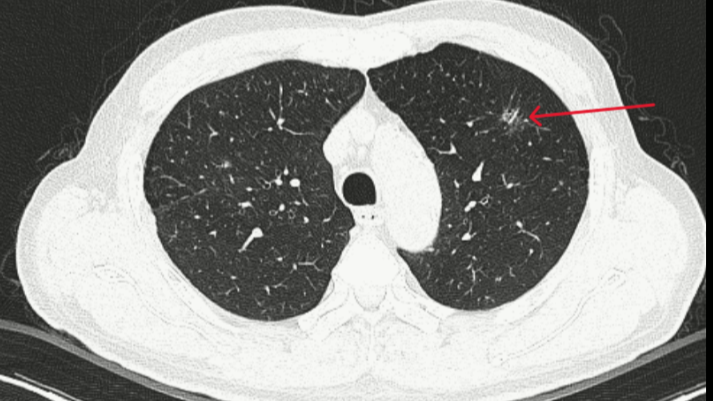

Tại Bệnh viện Bạch Mai, nam bệnh nhân ở Ninh Bình được AI phát hiện tổn thương thùy phổi phải và nguy cơ ung thư ác tính. Bệnh nhân đến khám tổng thể, không có dấu hiệu gì điển hình, ngay khi chụp X quang cũng chỉ phát hiện có đám mờ ở phổi.

Dù được làm thêm các xét nghiệm cận lâm sàng khác như nội soi phế quản, cuống họng... cũng chưa có gì đáng chú ý. Tuy nhiên, khi đưa các chỉ số của bệnh nhân vào phần mềm và AI hỗ trợ phân tích cho thấy, bệnh nhân được xác định bị tổn thương ở thùy phổi phải và nguy cơ ung thư ác tính.

Từ gợi ý đó, bác sĩ quyết định cho bệnh nhân chụp CT lồng ngực. Kết quả đúng như phân tích, máy tự động đọc và nhận diện ra tổn thương với đám mờ phổi chính là triệu chứng thời kỳ đầu của ung thư phổi.